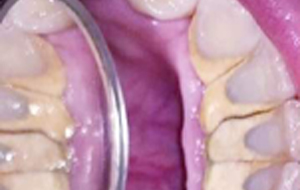

• Oral prophylaxis – A simple procedure of professional cleaning of teeth dislodges the plaque deposits on the teeth and hence maintains the health of the gums. This procedure should be done at an interval of 6 months.